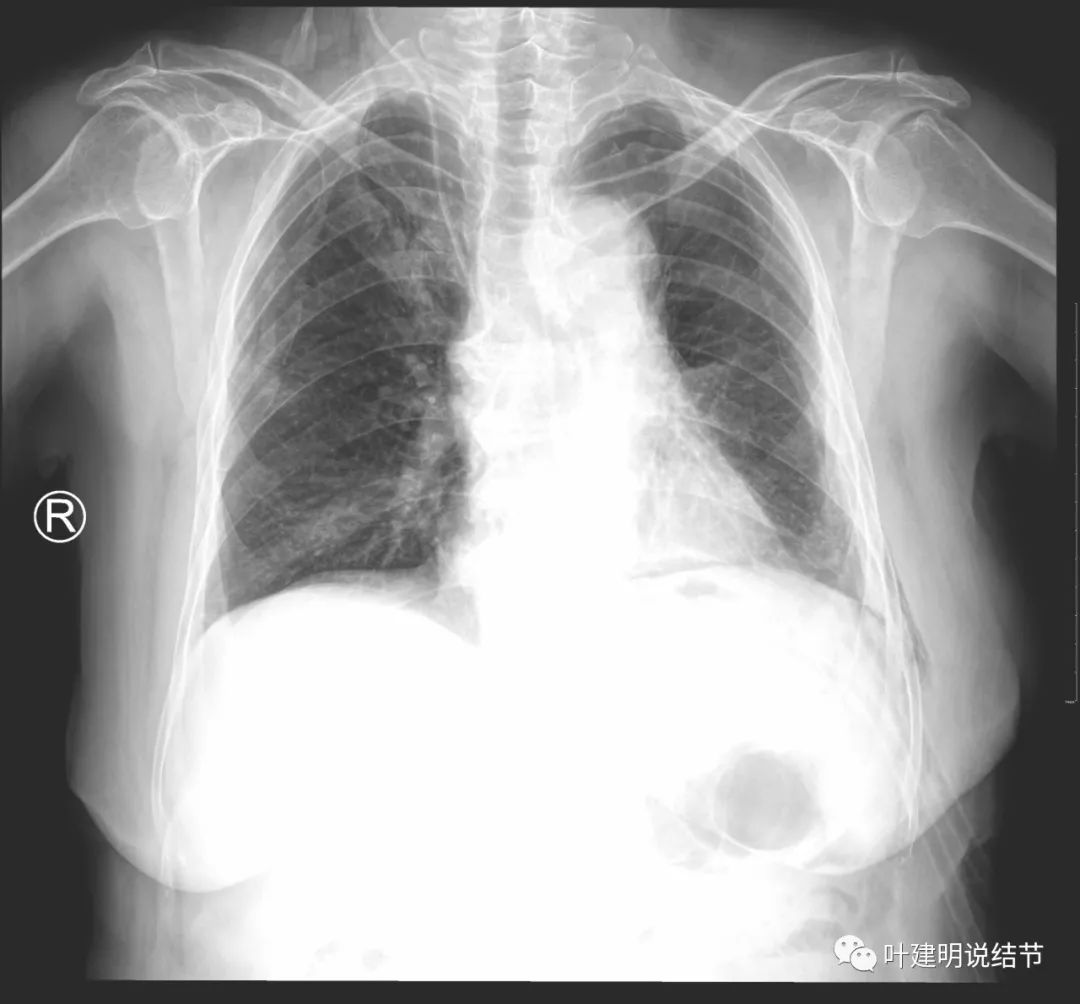

手术非常成功!历时约2个半小时。术后我们予以加强抗炎化痰、雾化吸入以及支持治疗。术后第一天,患者就能下床行走活动,下面是术后第一天胸片的情况:

此后恢复均顺利,由于年纪大,我们让其血常规示白细胞完全正常,中性粒细胞比例正常,胃纳活动均如常后于术后第11拔除胸管并出院。下面是术后第10天(昨天)拍的胸片,恢复非常好: